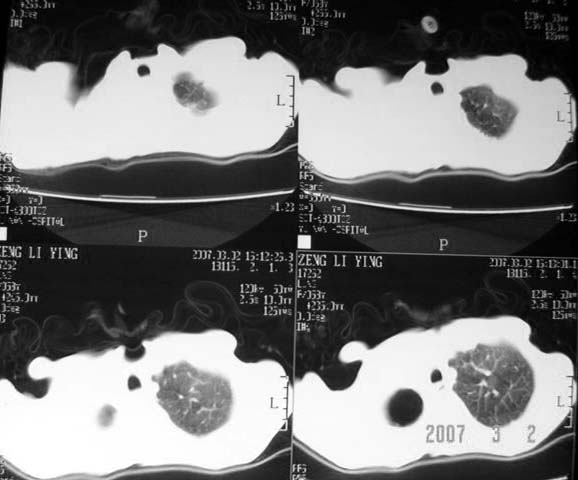

以下是引用dyqct在2007-3-2 22:04:00的发言:[br]考虑:1、右侧毁损肺伴支气管胸膜瘘(多条支气管与胸腔相通、液气胸);[br] 2、左肺浸润型肺结核。[br][br][br][br]